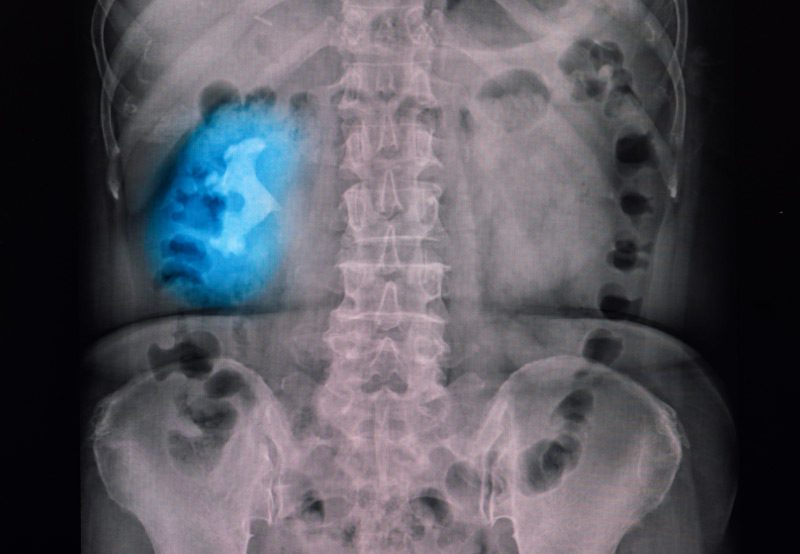

X-ray-showing-large-staghorn-kidney-stone

• Staghorn calculi: Large branching stones that occupy the renal pelvis and calyces